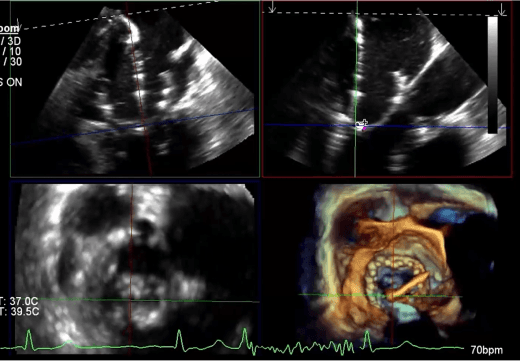

COMPLEX STRUCTURAL HEART

Multimodal display of devices gives proceduralists and teams a complete view of the entire case to refine processes, decision-making and future analysis.